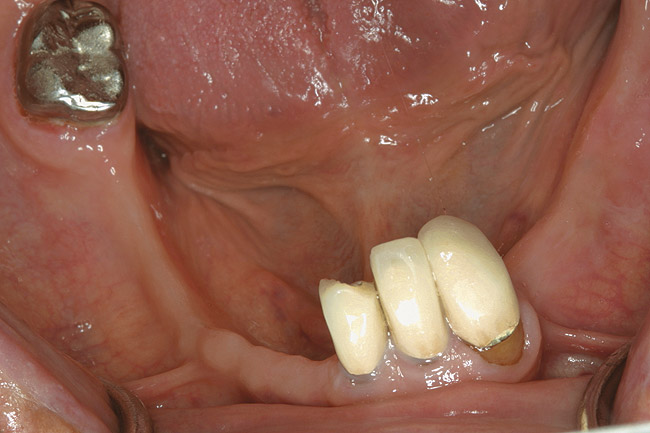

D2 root-surface lesions (Figure 3) are characterized by the dull surface demonstrated with D1 root-surface lesions. In addition, the surface feels sticky and somewhat soft when palpating with the side of the explorer. The examiner may notice that the root surface slightly resists gentle exploration over the root surface with the side of the explorer. Color changes in D2 root-surface lesions may range from dark yellow to orange/light brown. No cavitation of the root surface exists. The recommended treatment for D2 root-surface lesions includes remineralization with products (pastes and varnishes) containing fluoride, calcium, and phosphate. If the area is in the esthetic zone, the patient may request restoration, despite intact root structure.

It is common for practitioners to press the tip of the explorer into these root surfaces and decide to restore these “carious” areas. When pressing an explorer into a D2 root surface, a clinician may feel a definite softened surface or a “stick.” It is vital to either use the side of the explorer or visual inspection when determining these lesions. Aggressive exploration with the tip of the explorer may cavitate these root surfaces, which can lead to mechanical damage of the root surface and a decrease of the likelihood of successfully remineralizing the surface.

Figure 3  This root surface has a dull surface and is discolored. This indicates the progression of the demineralization/caries process. No cavitation has occurred due to this process. This root surface will feel slightly tacky and softened when exploring with the side of the explorer.

Figure 3